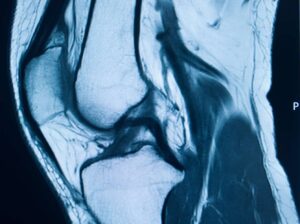

MRT Knie

• Untersuchung findet im Liegen auf einer fahrbaren Liege statt

• Patienten werden mit den Füßen voran bis maximal zum Oberkörper in die MRT-Röhre gefahren

• der Kopf kann während der Untersuchung außerhalb der Röhre bleiben